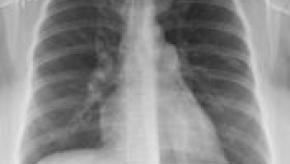

Read ArticleDoes ACPA Increase the Risk of Interstitial Lung Disease?

The anti-citrullinated peptide (anti-CCP or ACPA) antibody assay has a specificity of greater than 90% for rheumatoid arthritis and is associated with worse articular outcomes.